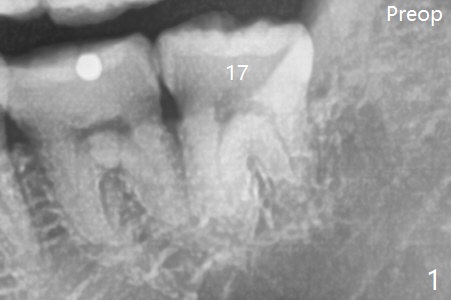

A 40-year-old man requests extraction of the teeth #17 and 32 (Fig.1).